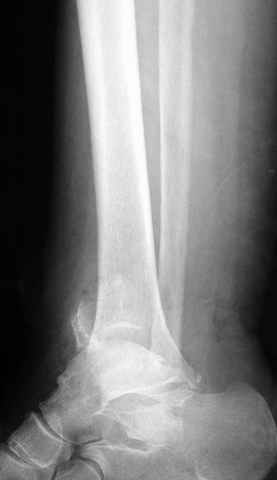

-С появлением новых имплантов, которые делятся на правые и левые, задней или латеральной аппликации, жесткие с локинг концепт, которые сидят на кости анатомически, применение 1/3 тубулярных пластинок

отходит на второй план из-за ее слабости. Если применить 2 пластины уложенные друг на друга, слабость этих пластинок можно скомпенсировать.

Слабая несостоятельная пластина приводит к вальгусной деформации и риск осложнений нарастает, особенно если линия перелома находится выше

метафизарной зоны, в диафизе, где имеется риск замедленного сращения, тогда адекватно применение более жесткой конструкции 3.5 мм динамической компрессионной пластины.

При косых переломах малоберцовой кости применение пластин отличается от обычных, показание antiglade technique-методика против скольжения, потому что укорочение длины малоберцовой кости чреваты ранними артрозами.

Из работ Ramsey and Hamilton, Yablon et., укорочения на 1мм

малоберцовой кости, уменьшает на 42% контактную поверхность между

малоберцевой и таранной кости, которое в свою очередь приводит к

увеличению давления на остальные части суставной поверхности, что

является предпосылкой раннего артроза.